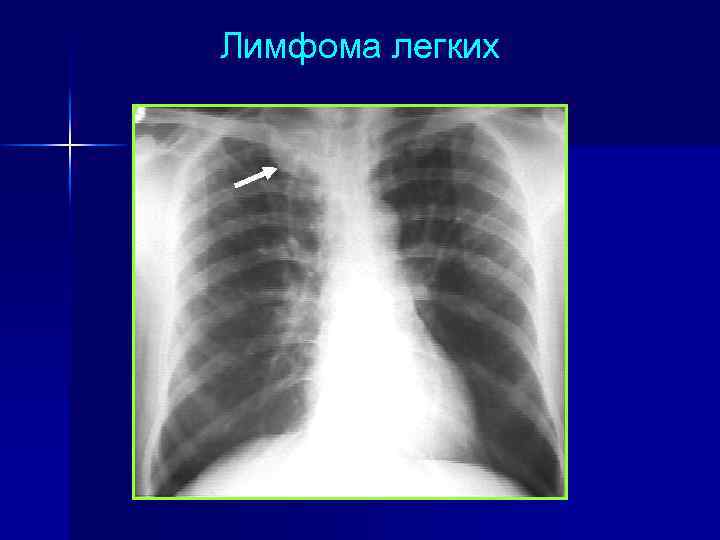

Лимфома легких